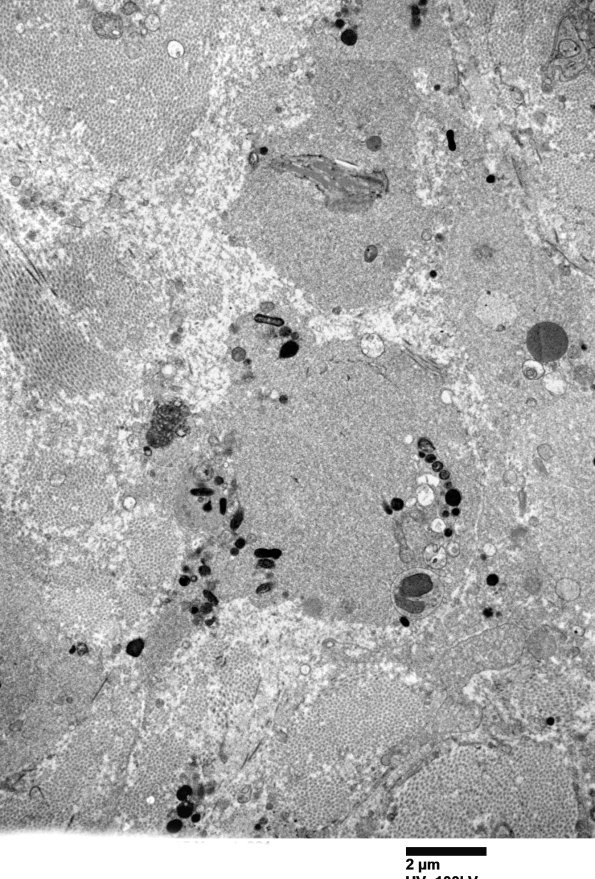

Within collagenous areas swollen structures were encountered which consist of autophagic vacuoles and tubulovesicular elements. We think these are swollen regenerative structures similar to axonal growth cones, likely by deviation into an area not conducive to regeneration. (electron micrographs)